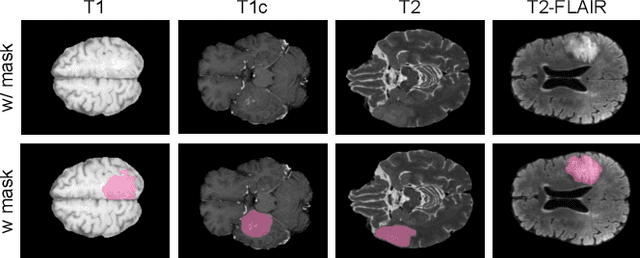

Abstract:Gliomas are brain tumours that stand out for their highly lethal and aggressive nature, which demands a precise approach in their diagnosis. Medical image segmentation plays a crucial role in the evaluation and follow-up of these tumours, allowing specialists to analyse their morphology. However, existing methods for automatic glioma segmentation often lack generalization capability across other brain tumour domains, require extensive computational resources, or fail to fully utilize the multi-parametric MRI (mp-MRI) data used to delineate them. In this work, we introduce GBT-SAM, a novel Generalizable Brain Tumour (GBT) framework that extends the Segment Anything Model (SAM) to brain tumour segmentation tasks. Our method employs a two-step training protocol: first, fine-tuning the patch embedding layer to process the entire mp-MRI modalities, and second, incorporating parameter-efficient LoRA blocks and a Depth-Condition block into the Vision Transformer (ViT) to capture inter-slice correlations. GBT-SAM achieves state-of-the-art performance on the Adult Glioma dataset (Dice Score of $93.54$) while demonstrating robust generalization across Meningioma, Pediatric Glioma, and Sub-Saharan Glioma datasets. Furthermore, GBT-SAM uses less than 6.5M trainable parameters, thus offering an efficient solution for brain tumour segmentation. \\ Our code and models are available at https://github.com/vpulab/med-sam-brain .